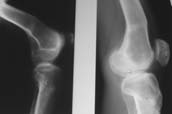

> Пациент В. 53 лет, травма в феврале 2009. ДЗ. Открытый оскольчатый перелом нижней трети голени. При боли поступлении выполено ПХО, аппарат Илизарова. В последующем проводили ВХО, резекция костных отломков, укорочение 6 см, рана зажила. Была выполнена остеотомия большеберцовой кости в проксимальном отделе, резекция. Производилось тракция.

> На последних рентгенограммах выявлено, что одновременно с "выращиванием" регенерата произошло низведение надколенника  на длину выращенного регенерата.

> Клинически: активное разгибание сохранено, объем движений в колене 180-110 градусов.  Черными стрелками обозначен верхний край надколенника с одной и с другой стороны. Красная стрелка обозначает пальпируемую связку надколенника.

> Причина - остеотомия выше места прикрепления связки надколенника.